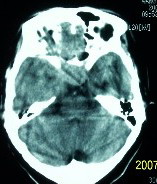

f    29岁   头闷  头晕1月余

鞍上脑膜瘤

肿瘤累及颅底前颅窝,部分层面见散在钙化,中心坏死。支持:脑膜瘤!

右额叶底部巨大等低混杂密度肿块,边界清楚,周围水肿轻度,明显占位效应。蝶鞍扩大,部分骨质破坏。

考虑脑膜瘤,建议增强扫描进一步检查。

可能是颅咽管瘤吧

考虑鞍区脑膜瘤可能性大。

蝶鞍受压吸收,可以排除室管膜瘤。肿瘤最大层面不在蝶鞍可以排除垂体瘤。支持脑膜瘤